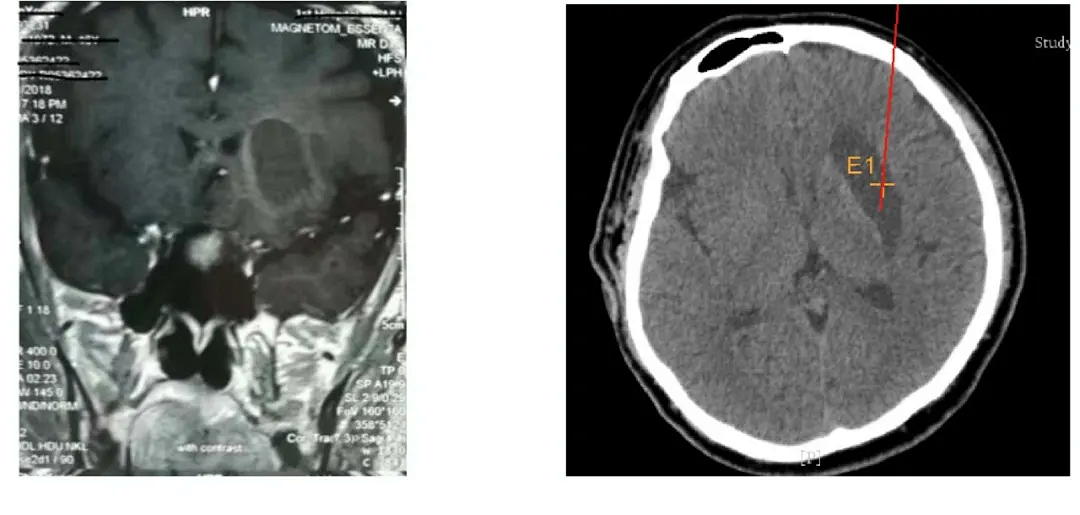

實(shí)施腦出血手術(shù)中

機(jī)器人輔助立體定向外科手術(shù)系統(tǒng)操作精度高,定位準(zhǔn)確,精度可達(dá)到0.5mm。如依靠機(jī)器人施行腦手術(shù),患者始終處于清醒狀態(tài)下,半小時(shí)左右手術(shù)即完成。術(shù)后3天,大部分患者就可走出醫(yī)院,實(shí)現(xiàn)了微創(chuàng)傷,縮短了患者術(shù)后恢復(fù)時(shí)間,手術(shù)成功率高。